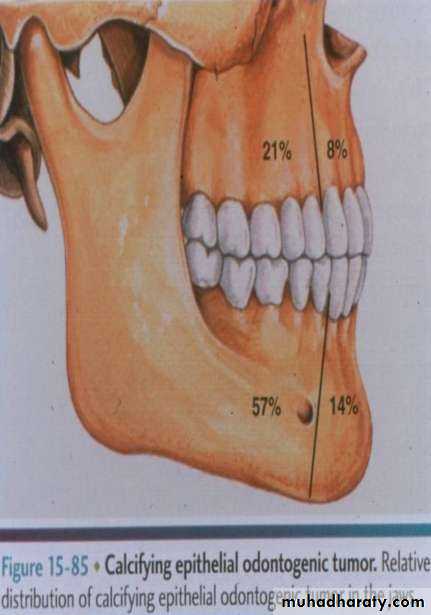

• Calcifying epithelial odontogenic tumor

• Benign , locally aggressive tumor originated from the rest of dental lamina and/or REE .• " Bindborg" tumor.

• Clinically :• Affect adult ,40 years.

• More common in the mandible

• Molar and premolar region